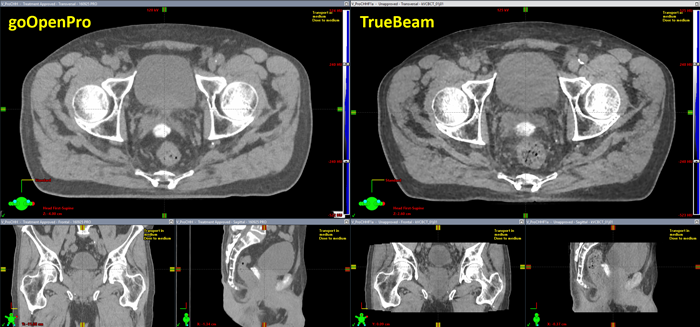

If we look at typical TrueBeam CBCT images (right), we have to say that bulk-density overrides do not necessarily come to our mind:

(Image quality of goOpenPro (left) and TrueBeam (right). Window/levelling is identical.)

The GPU-based iterative CBCT reconstructor (iCBCT), which we implemented in 2021, produces excellent images with very good low contrast resolution. The TrueBeam image looks sharper than the image of the goOpenPro, but this is mainly because the CBCT image has a resolution of 0.9 x 0.9 mm (matrix size: 630 (after couch enlargement) x 512 px), whereas the resolution of the goOpenPro image shown is 1.2 x 1.2 mm (512 x 512 px).

The quickest way to find out which is which is scan length. The CBCT image shown is about 16 cm long. However, this can be misleading if Extended Scan (multiple consecutive acquisitions are combined in one reconstruction) is used.